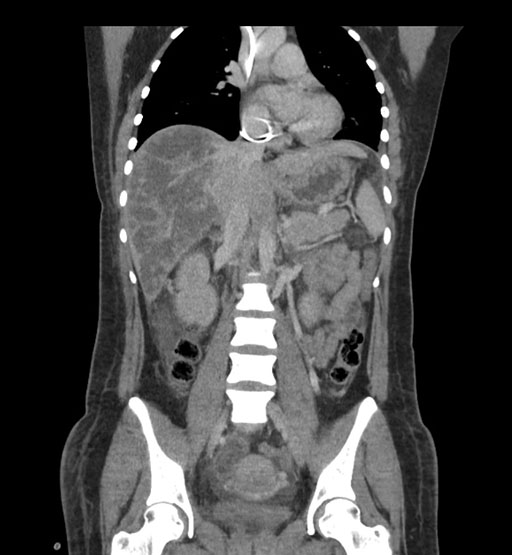

Coronal Arterial

Imaging analysis

Based on initial findings, which issue(s) would you be most concerned about?